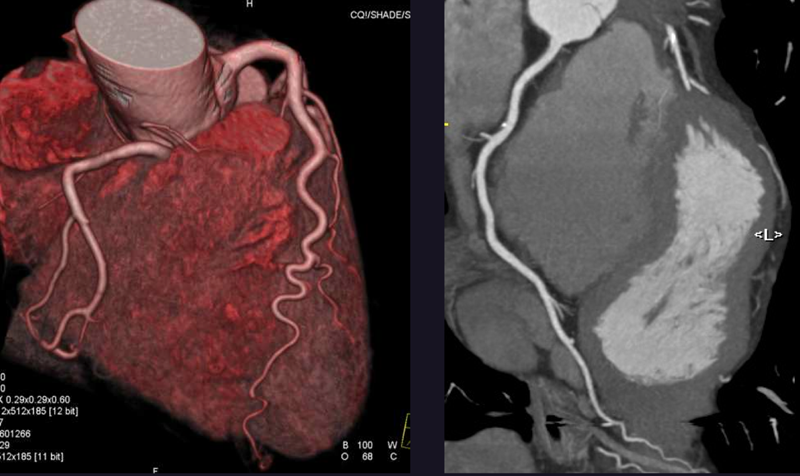

A 78-year-old patient presents with chest pain. Can you make the diagnosis?

Patients suspected of having coronary stenoses may benefit from ultra-high-resolution CT, according to a recent study that showed high diagnostic confidence in severely calcified coronary atherosclerotic disease.